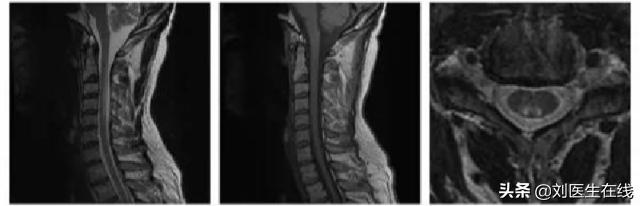

随后,医生又让吴老先生去做了包括 肌电图、血常规、磁共振 在内的一系列检查,其结果都证明医生的判断是正确的。

脊髓亚急性联合变性,医学上简称为 亚急性联合变性(SCD) ,主要是由于 人体内对于维生素B12的摄取、吸收、结合、转运、代谢产生了障碍 ,从而导致人体内维生素B12的含量过低,进而引发的 一种中枢和周围神经系统变性的疾病 。

病变主要涉及脊髓后索、侧索及周围神经等部位,医学上的临床表现基本是类似吴老先生这样的双下肢深感觉缺失、感觉性共济失调、痉挛性瘫痪及周围性神经病变等,也伴有贫血的情况。